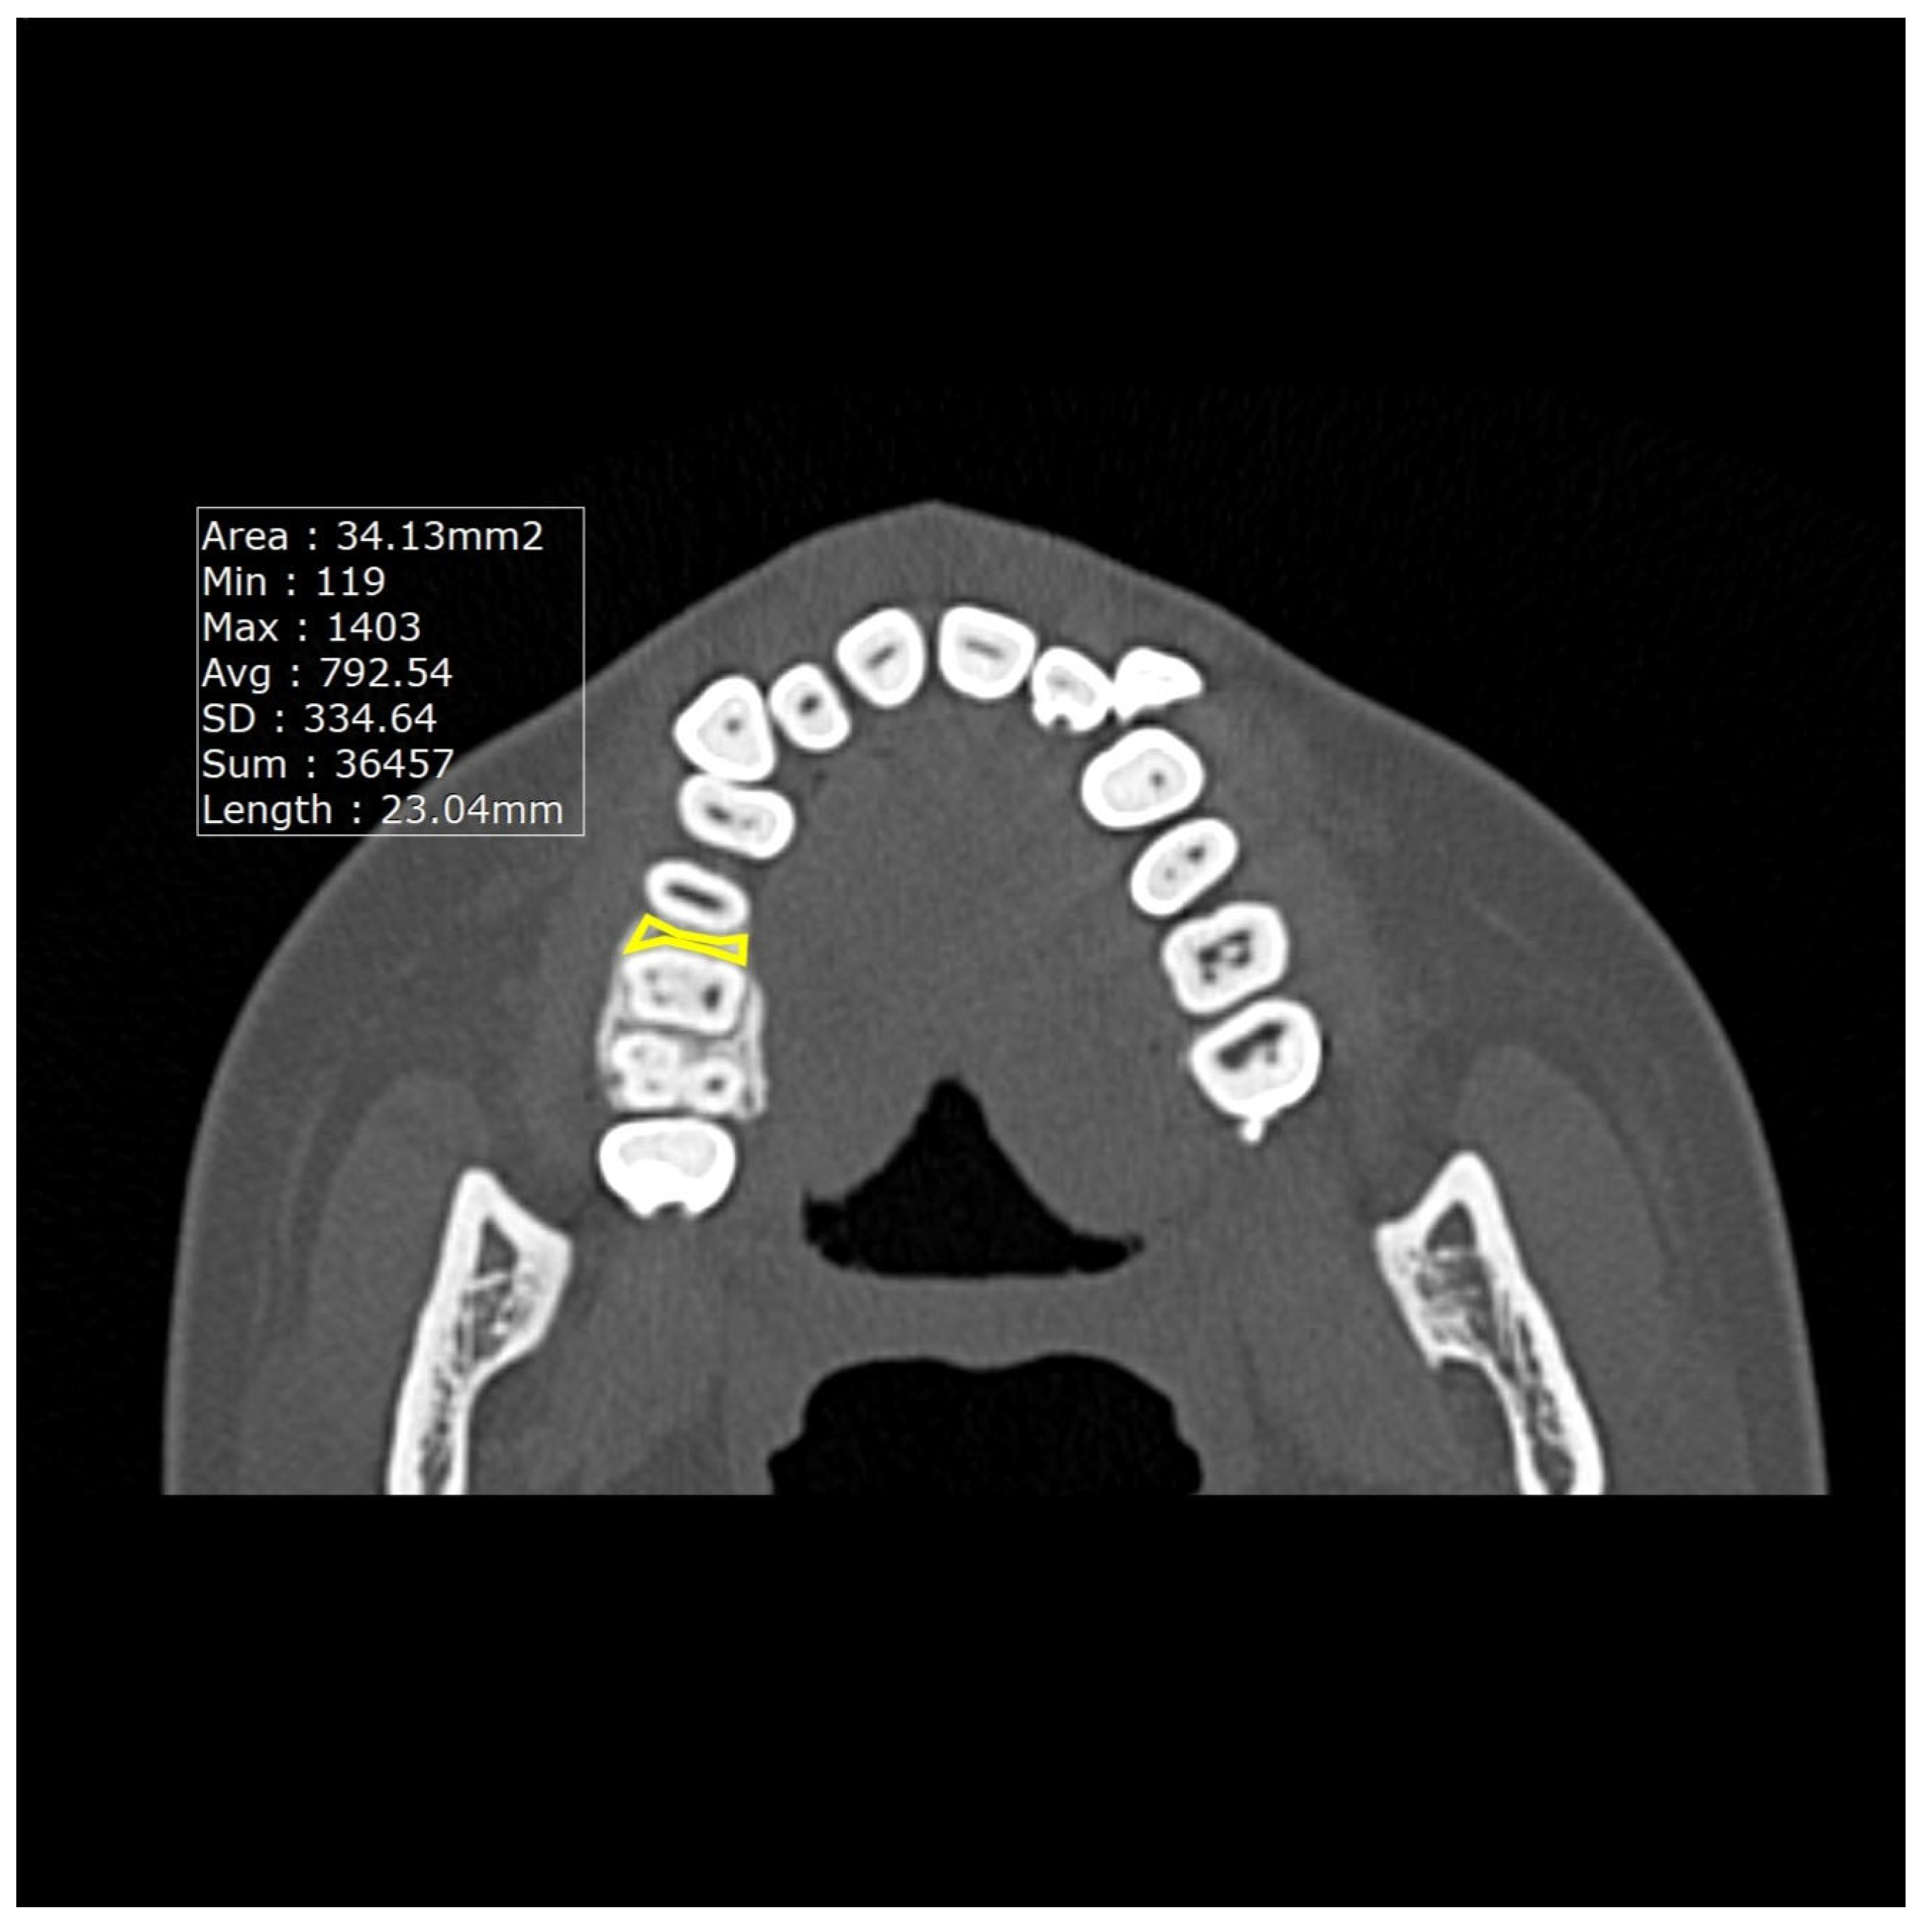

2.3. CT Imaging Analysis

| Tmax3 | thickness between the maxillary canine and first premolar |

| Tman3 | thickness between the mandibular canine and first premolar |

| Tmax6 | thickness between the maxillary premolar and first molar |

| Tman6 | thickness between the mandibular premolar and first molar |

| Dmax3 | density between the maxillary canine and first premolar |

| Dman3 | density between the mandibular canine and first premolar |

| Dmax6 | density between the maxillary premolar and the first molar |

| Dman6 | density between the mandibular premolar and the first molar |